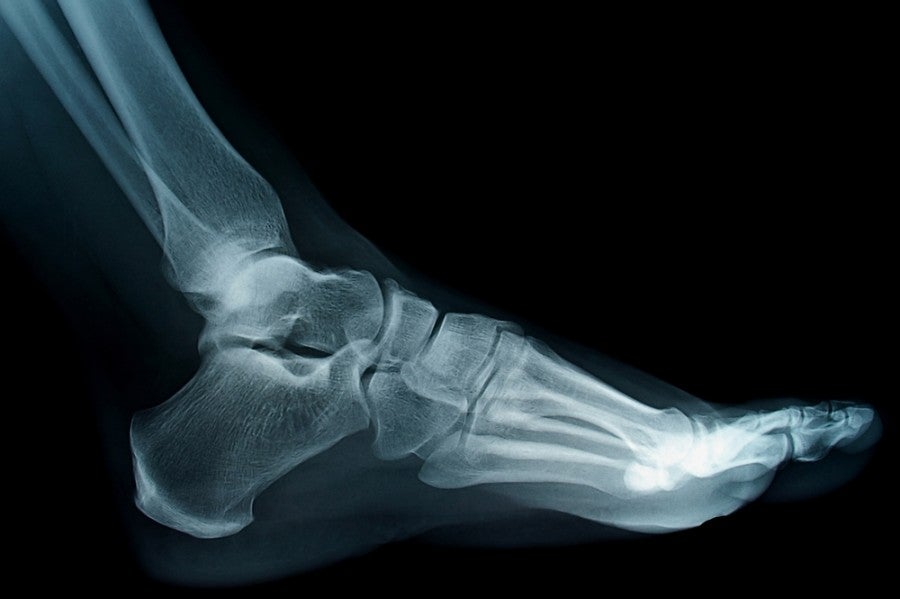

I crawled up to my seat and sat in confusion and concern, trying to process how my right foot was suddenly so sensitive that even drying it with a towel caused me to wince. I would not be getting back in the water.

The nurse did some intake, checked my vitals, and called the doctor. Twenty-five minutes later, Dr. Ibiza pulled up on his racing motorcycle and I repeated my complaints to him as he stripped off his protective leather outerwear. He inspected my foot, slathered it with brown liquid, wrapped it with a thin bandage, and informed me I had an infection. (Apparently, my stubborn walking had led to a blister which had led to a cut which had led to a welcome party for Mediterranean Sea bacteria.) Moto-doctor suited back up, declined my request for crutches, and was back on his bike less than ten minutes after he'd arrived—now with 125 of my Euros ($136) in his account.

It took me about an hour to walk the three blocks to the pharmacy, where I filled my prescription for antibiotics and bought a protective boot, the strongest painkillers legally allowed in Spain, and in a stroke of MacGyver-worthy genius, a set of bright-orange water wings to place around my foot. I wanted to ensure proper cushioning for the four airports I'd have to schlep through to get home the next day— Ibiza, Barcelona, Frankfurt and Los Angeles. And all my flights were in coach.